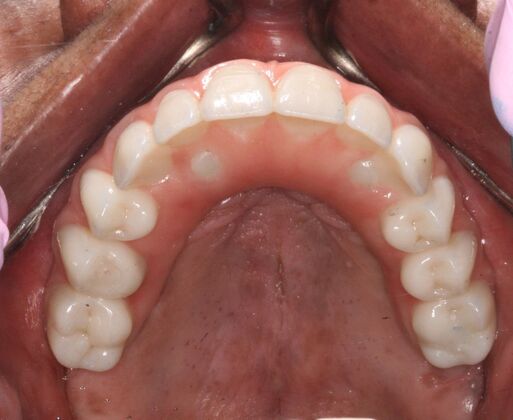

Patient had severe gum disease and she started losing her teeth one by one and was very unhappy with her partials. Patient was holding on to the very last few teeth in her mouth which were loose, in order to avoid wearing dentures! When she discovered Dr Bidra, and was informed that she could get transformed in one single day, she and her husband were immediately motivated. Patient had her teeth extracted, implants placed and new teeth installed all in one day.

Procedures : extractions, implants, All on 4 , Teeth in a day, no bone grafting and full mouth reconstruction with monolithic zirconia bridges.